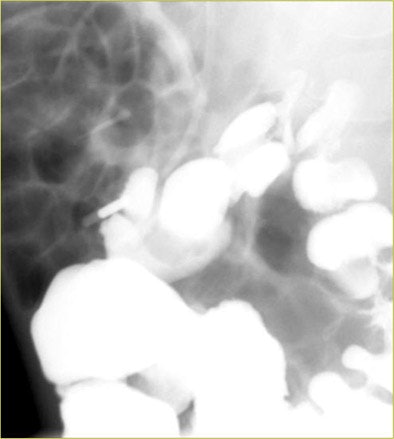

![]() |

| A white strip appeared superolaterally to the bladder in a voiding cystourogram study. The physicians were unsure whether it represented reflux or bowel wall. Instead of repeat fluoroscopy, they repeated the run in LFH mode, which clearly showed that the anatomy was bowel wall. |